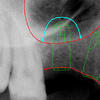

So kann sie auch bei mehreren Bildern oder auch bei Schwangeren den Körper nicht belasten. Weil das Bild sogar 50-100-mal vergrössert als eine normale intraorale Röntgenaufnahme ist, kann auch der kleinste Teil nicht unsichtbar bleiben um eine exakte Diagnostik zu erreichen. Die Aufnahme mit dem Computer analysierend, können wir nicht nur die Versorgung planen oder sogar modellieren sondern während der Behandlung Schritt für Schritt kontrollieren. Einige Highlights von diesem Prozess können Sie bei einer Implantation unten links, als Illustration sehen.